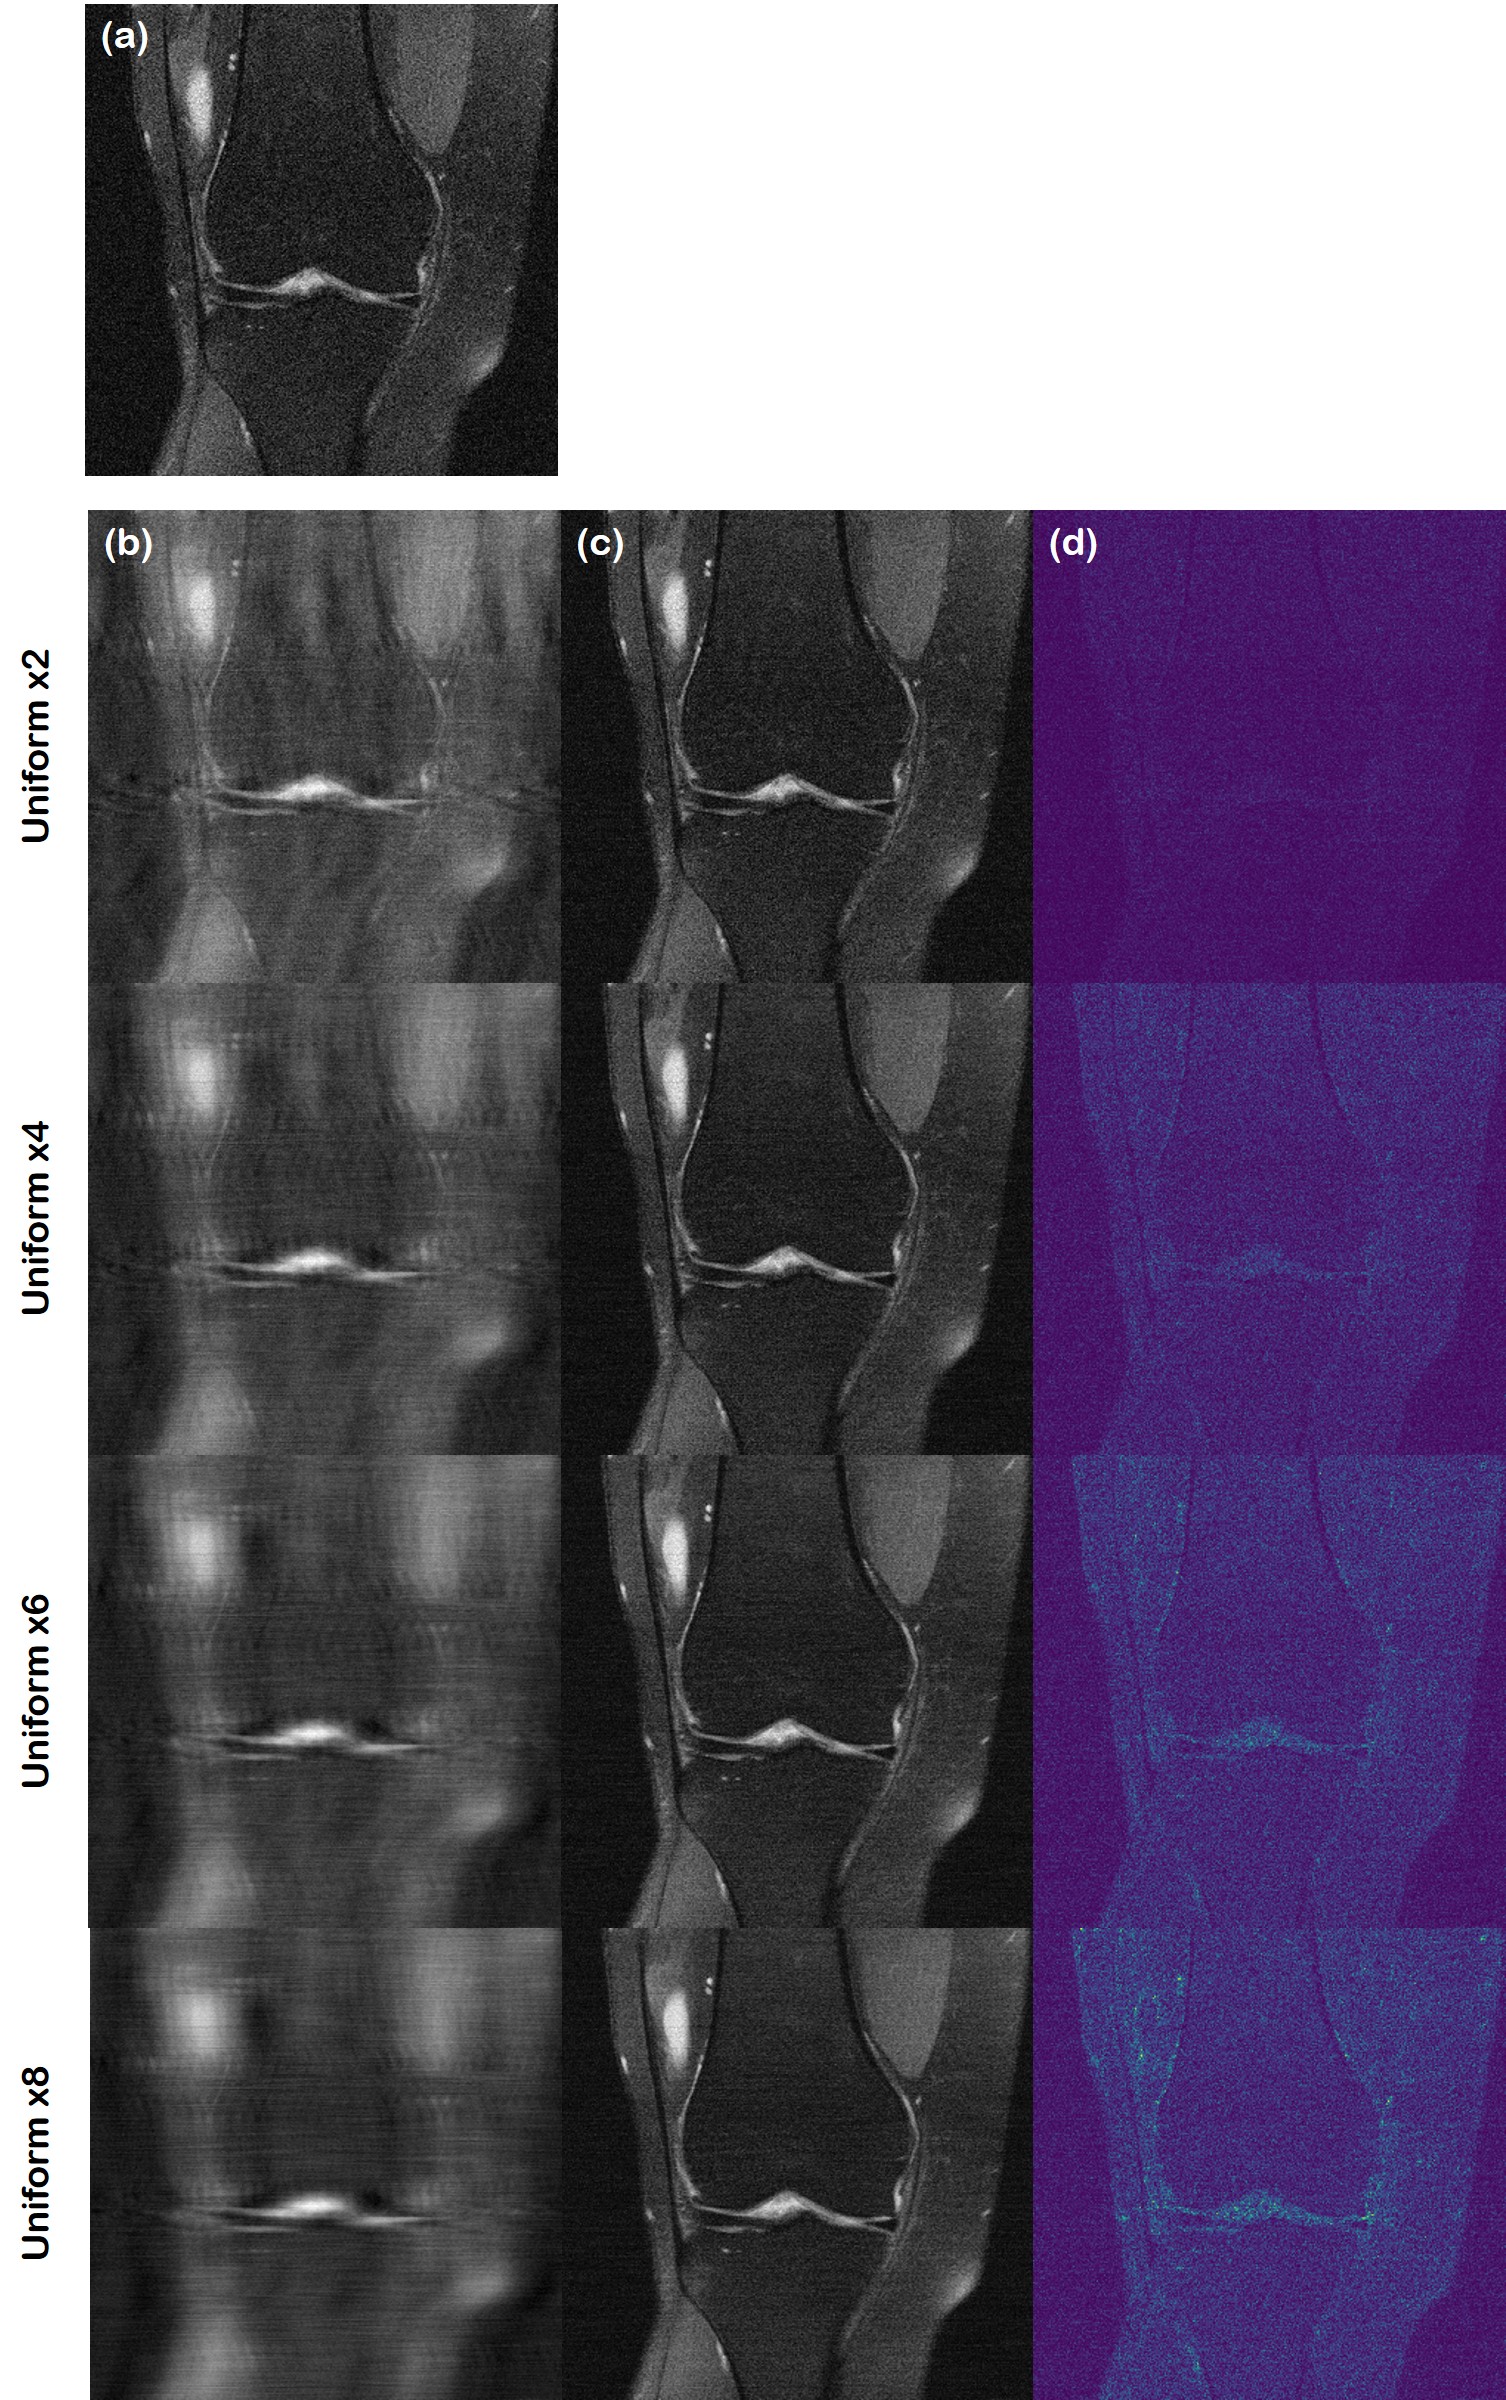

Fig. 8: Quantifying the uncertainty of reconstruction. (a) Ground truth, (b) aliased image from sub-sampling, (c) mean of the reconstruction, (d) standard deviation of the samples: range is set to [0, 0.02] (on Viridis colormap). From the 1stst{}^{\text{st}} row to the 4thth{}^{\text{th}} row, the acceleration factor grows from ×2absent2\times 2 to ×8absent8\times 8.

Due to this generative nature, we can run multiple reconstructions in parallel, and quantify the uncertainty of the prediction, as depicted in Fig. 8. Here, the ground truth, and the aliased images are shown in Fig. 8 (a),(b), respectively. For the experiment, we take a batch size of 8, and run the reconstruction in parallel. The mean value of the reconstruction is shown in Fig. 8 (c), and the pixel-wise standard deviation values are shown in Fig. 8 (d). At low acceleration factors (×2absent2\times 2), we see very little variation between the different reconstructions. This indicates high confidence of the model, and hence we can conclude that the reconstruction is exact in all parts of the image. As the acceleration factor is increased, and the degree of aliasing artifacts become more severe, we see that the uncertainty increase in specific regions. Potentially, this measure of uncertainty can inform the practitioners on how much they should rely on the reconstruction, thereby deciding whether to use a different diagnostic tool. We additionally provide specific realizations, rather than the mean of the reconstruction, at each acceleration factor in supplementary video 1.